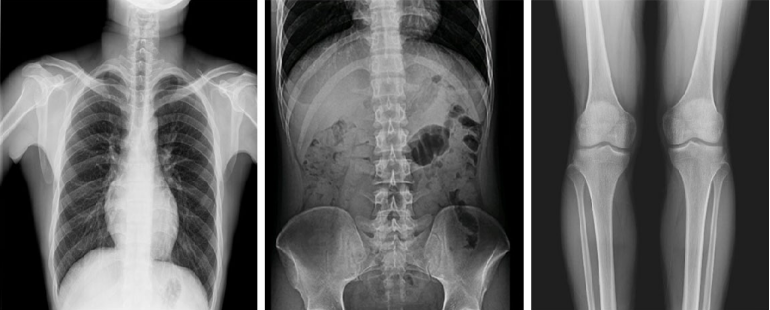

而且,影像采集幅面大,17×17英寸超大視野可覆蓋成年人的全胸全腹,并且能在連續(xù)動(dòng)態(tài)中實(shí)時(shí)高清點(diǎn)片,從而達(dá)到精準(zhǔn)診斷的目的。設(shè)備靈活高效的多維度運(yùn)動(dòng)設(shè)計(jì),也帶來了更加智能化、人性化操作體驗(yàn),可大幅提升檢查效率。

與此同時(shí),普利德動(dòng)態(tài)平板DRF還具有全身拼接功能,尤其適用于全脊柱和全下肢攝影,為臨床提供高精度圖像,輔助脊柱畸形矯形治療、康復(fù)檢查。